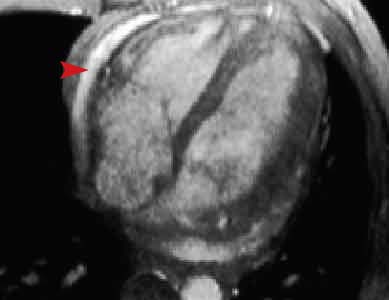

This two chamber long axis gradient echo image shows a bright fluid collection in the pericardial space (arrowhead). If this fluid accumulated quickly, the patient may experience symptoms of cardiac tamponade.

Pericardial effusion is fluid in the pericardial space. Patients can present with pain, dyspnea, pericardial friction rub, and hemodynamic compromise. Common causes include neoplasm, uremia, autoimmune disease, inflammation, viral infection, tuberculosis, and hemopericardium. A small amount of fluid is relatively inconsequential, but large or rapidly accumulating effusions can cause tamponade.

Cardiac MRI can be used to characterize pericardial effusions and assess the pericardium. Major indications for cardiac MRI is to evaluate for loculated pericardial effusions and pericardial adhessions, determine if an effusion is complicatated (hemorrhagic vs. non-hemorrhagic), measure pericardial thickness, and assess for pericardial enhancement. On spin-echo imaging, simple effusions have low signal intensity on T1-weighted imaging and a high signal intensity on T2-weighted imaging. Chylous and hemorrhagic effusions have a higher signal on T1-weighted imaging. Cardiac MRI is also useful in patients with inconclusive echocardiographic exams.